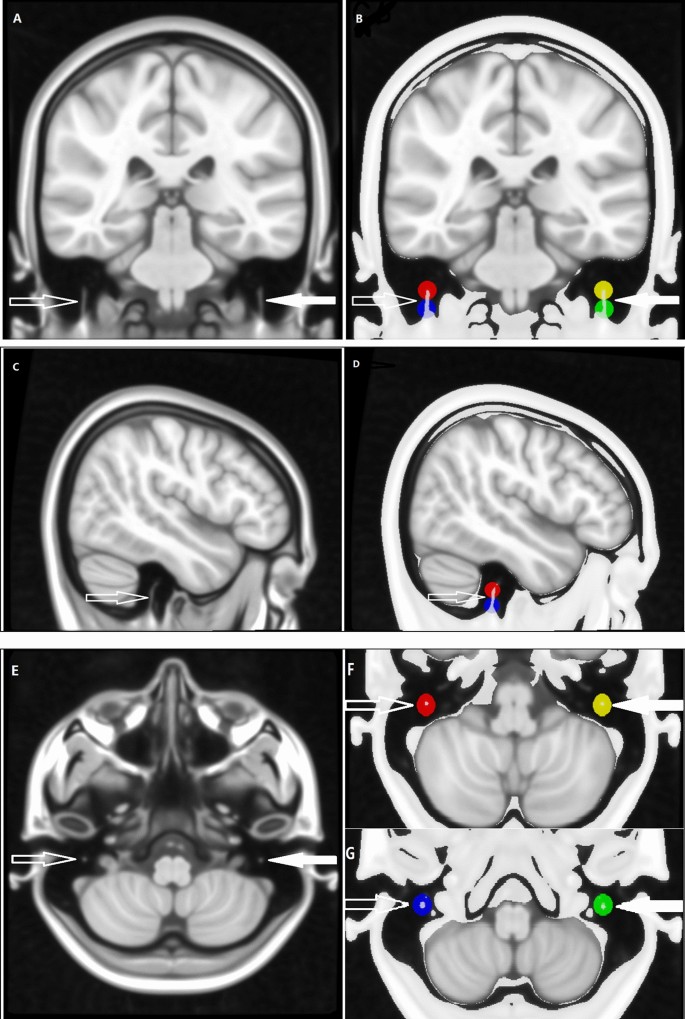

To construct group-level common template space of 0.4 mm3 voxel size, the 0.5 mm3 voxel of MNI152_T1_0.5 mm brain template (International Consortium for Brain Mapping) was normalized and resampled to 0.4 mm3 template using the "old norm" method of SPM12, which named MNI152_T1_0.4 mm template in the present study (Fig. 1). By using FSL-maths, a group of 4 common spherical seed regions (5 mm in diameter) was calculated and placed on the mastoid segment of intratemporal facial nerves, bilaterally and symmetrically (Fig. 2).

The symmetrically spherical ROIs (right: red and blue; left: yellow and green) with the same diameter of 5 mm, were set on intratemporal facial nerves (right: hollow arrow; left: solid arrow) in the 0.4 mm3 voxel MNI common space (named MNI152_T1_0.4 mm).